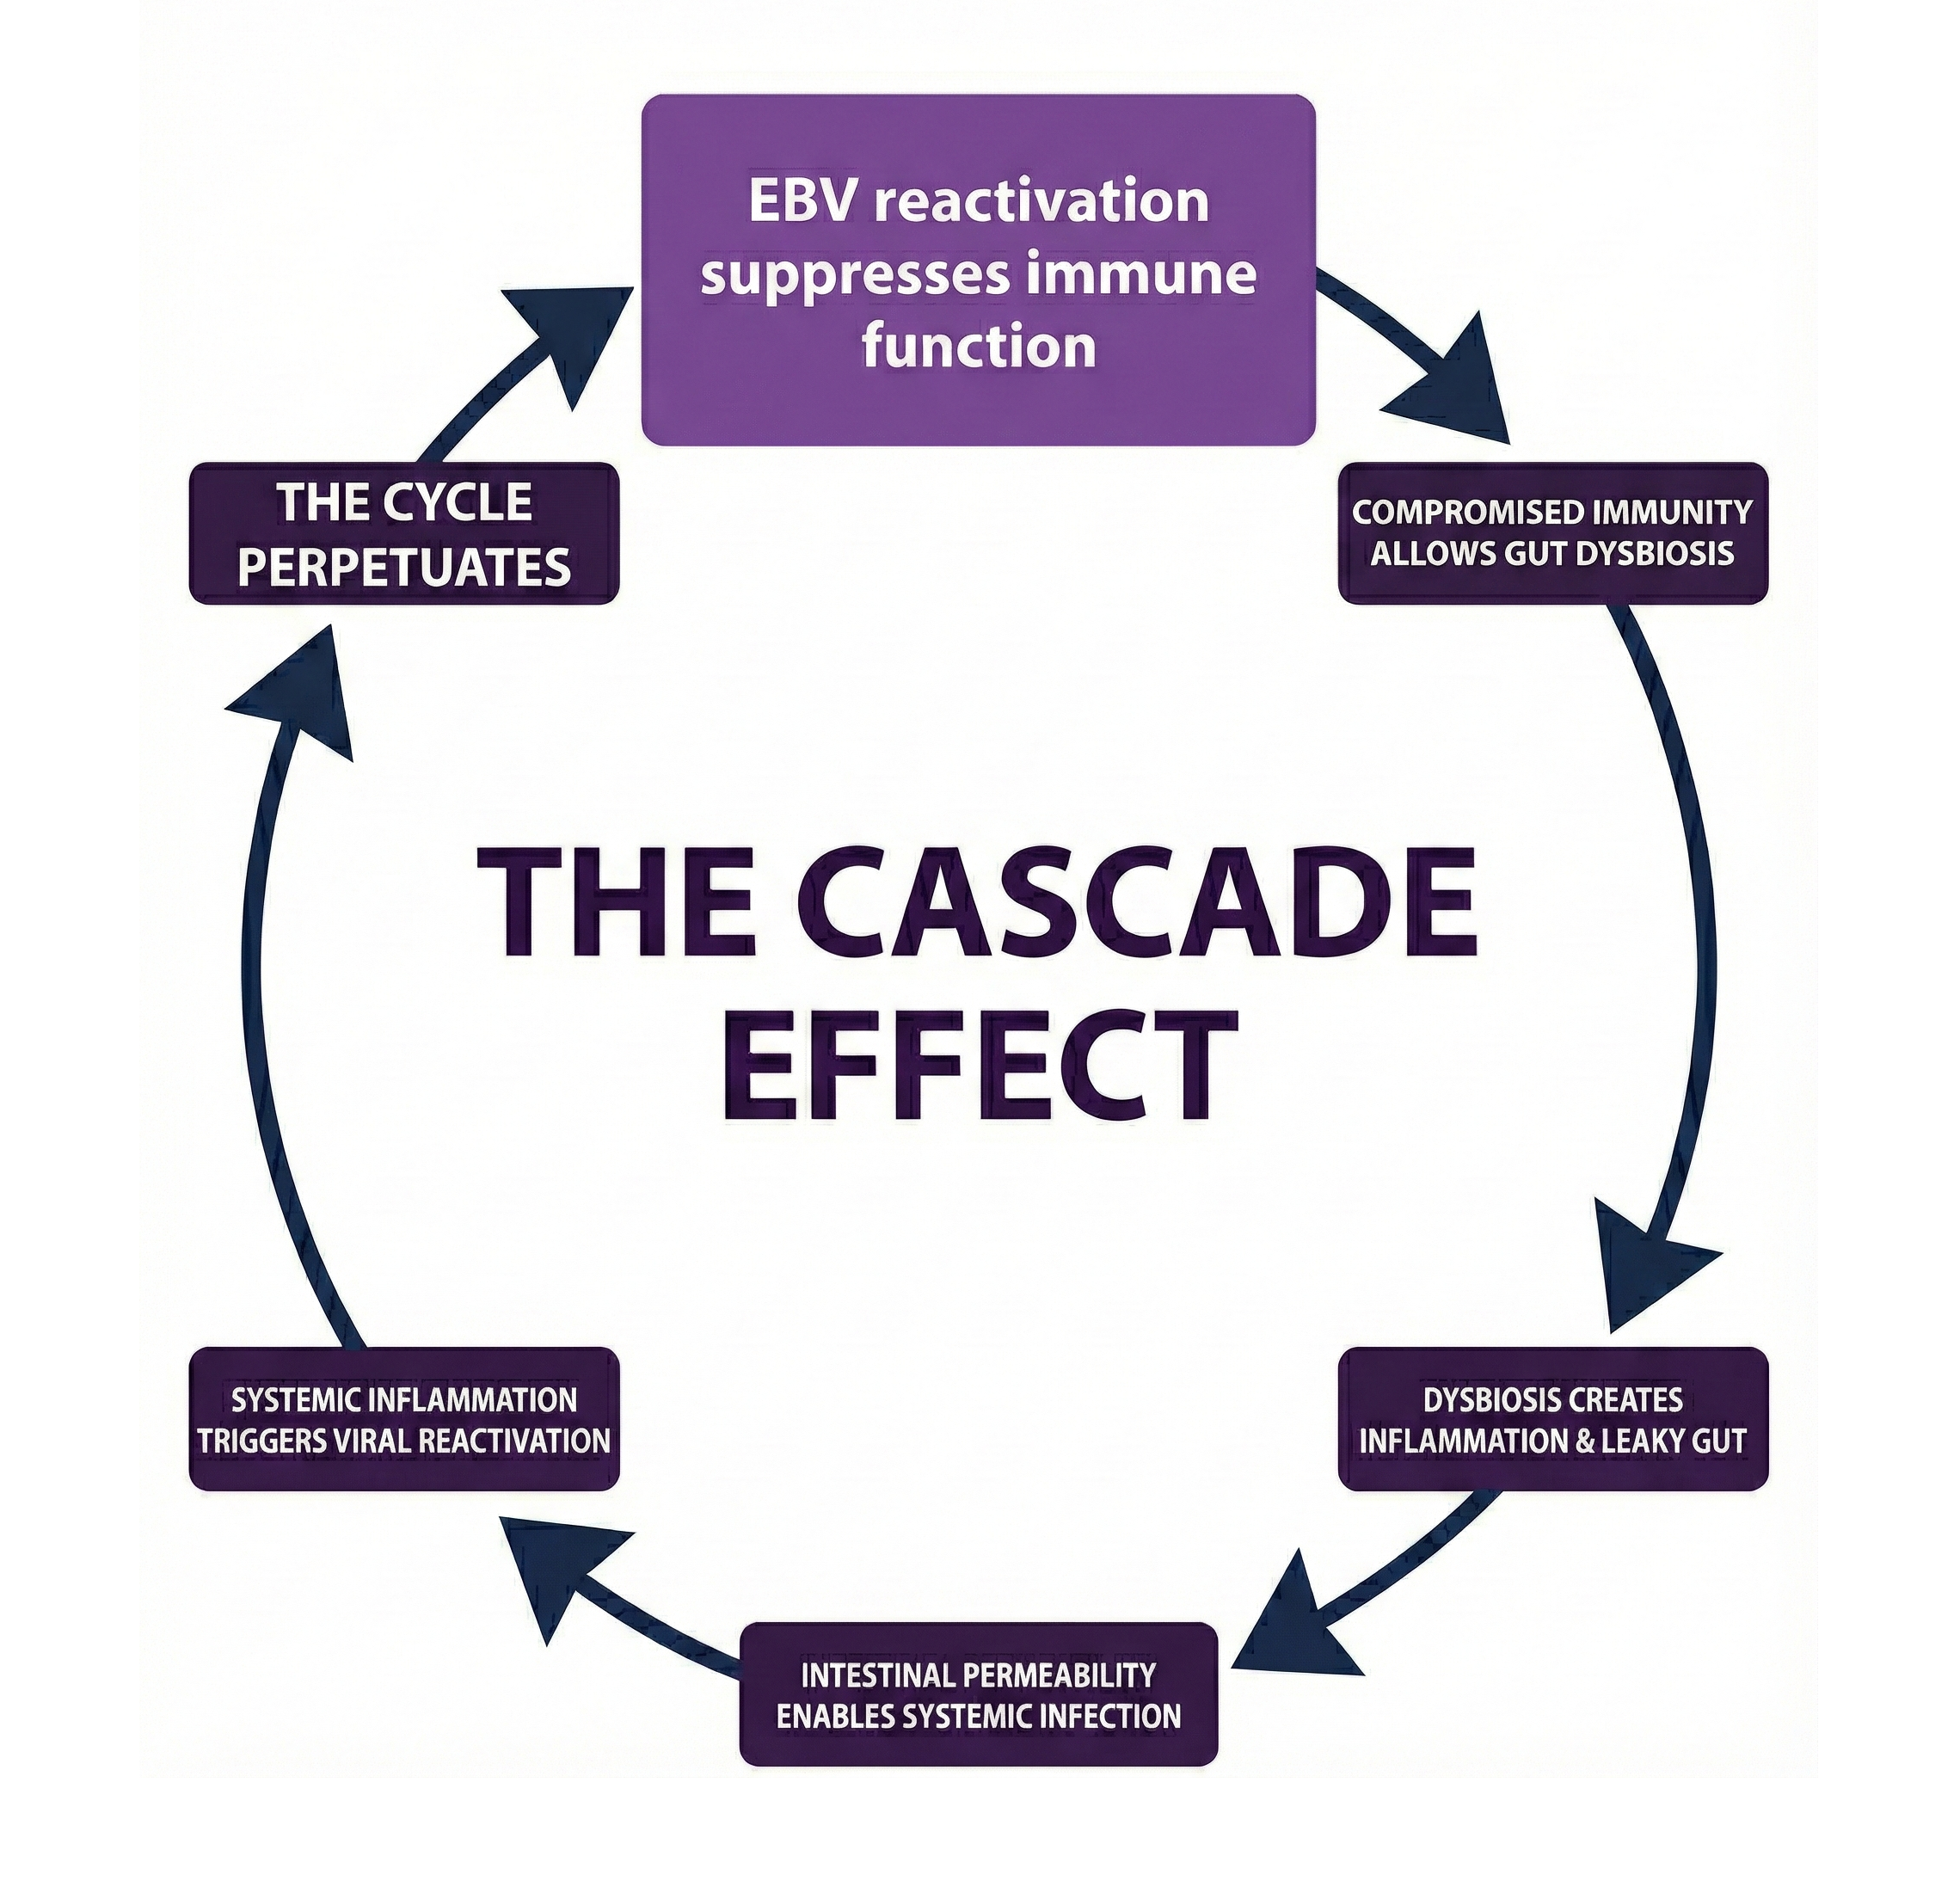

The Cascade Effect

This is why addressing single infections fails. You must approach the entire web systematically.

Viral Persistence: Masters of Manipulation

Viral persistence has reached new levels of sophistication. Epstein-Barr virus, present in 95% of adults, has mastered the art of dormancy and reactivation. It doesn’t just hide—it actively manipulates immune responses, creating an environment where other pathogens thrive. Recent research links EBV reactivation to everything from Hashimoto’s thyroiditis to certain lymphomas.

Epstein-Barr virus deserves special attention. It’s not just another infection—it’s a master manipulator that creates conditions for other pathogens to flourish. The virus integrates into B-cell DNA, establishes latency in multiple tissue types, and reactivates strategically when the immune system is compromised.